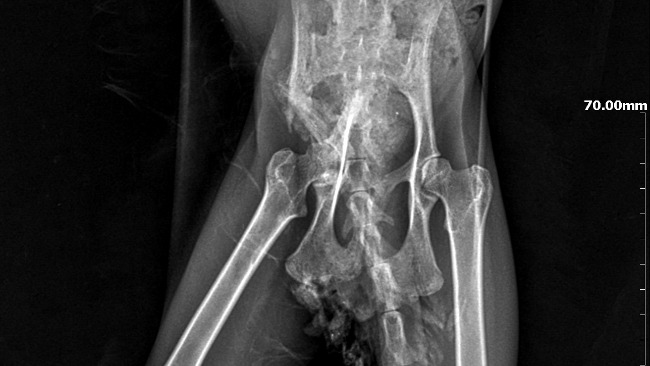

Charlotte przeszła więcej, niż powinno spaść na jedno kocie życie – złamanie miednicy, megacolon, FIP… każda z tych diagnoz osobno byłaby trudna, razem – stanowiły ogromne wyzwanie. Ale Charlotte nie była w tej walce sama. Byliście z nami – i to właśnie dzięki Wam ta historia kończy się dobrze.